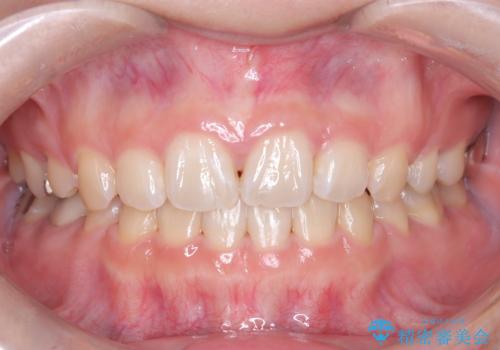

目立たない矯正で口元の突出感を解消

今回の矯正治療では、前歯を大きく後退させるスペースを確保するため、計画通り上下左右の第一小臼歯を抜歯しました。装置には、上顎には目立たない裏側矯正(舌側矯正)を、下顎には透明な審美ブラケットを使用するハーフリンガル矯正を採用しました。抜歯によってできたスペースを最大限に活用し、前歯を効率よく後方へ移動。治療の結果、口元の突出感が大幅に解消され、Eライン(横顔の美しさの基準)も改善しました。人目を気にすることなく治療を完遂し、自信の持てる美しい横顔を獲得していただけました。